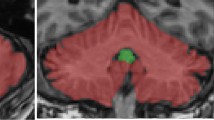

Perception of our linear motion — heading — is critical for postural control, gait, and locomotion, and it is impaired in Parkinson’s disease (PD). Deep brain stimulation (DBS) has variable effects on vestibular heading perception, depending on the location of the electrodes within the subthalamic nucleus (STN). Here, we aimed to find the anatomical correlates of heading perception in PD. Fourteen PD participants with bilateral STN DBS performed a two-alternative forced-choice discrimination task where a motion platform delivered translational forward movements with a heading angle varying between 0 and 30° to the left or to the right with respect to the straight-ahead direction. Using psychometric curves, we derived the heading discrimination threshold angle of each patient from the response data. We created patient-specific DBS models and calculated the percentages of stimulated axonal pathways that are anatomically adjacent to the STN and known to play a major role in vestibular information processing. We performed correlation analyses to investigate the extent of these white matter tracts’ involvement in heading perception. Significant positive correlations were identified between improved heading discrimination for rightward heading and the percentage of activated streamlines of the contralateral hyperdirect, pallido-subthalamic, and subthalamo-pallidal pathways. The hyperdirect pathways are thought to provide top-down control over STN connections to the cerebellum. In addition, STN may also antidromically activate collaterals of hyperdirect pathway that projects to the precerebellar pontine nuclei. In select cases, there was strong activation of the cerebello-thalamic projections, but it was not consistently present in all participants. Large volumetric overlap between the volume of tissue activation and the STN in the left hemisphere positively impacted rightward heading perception. Altogether, the results suggest heavy involvement of basal ganglia cerebellar network in STN-induced modulation of vestibular heading perception in PD.